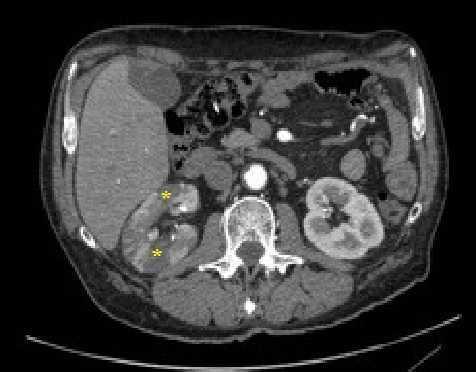

Varón de 54 años de edad con antecedentes personales de hipertensión arterial, diabetes mellitus tipo 2, hipercolesterolemia, infarto de miocardio que requirió colocación de stent en descendente anterior y fumador activo. Estaba en tratamiento con ácido acetilsalicílico, simvastatina, enalapril, atenolol, metformina, insulina, furosemida y omeprazol. Consulta por segunda vez en 24 horas en el Servicio de Urgencias por dolor abdominal y vómitos de dos días de evolución. A la exploración física presentaba una presión arterial de 139/85 mmHg y una frecuencia cardíaca de 45 latidos por minuto, con una auscultación cardíaca y abdominal sin soplos. En la analítica destacaba una lactato deshidrogenasa de 2458 UI/l, siendo la previa del día anterior inferior a 500 UI/l, con creatinina de 0,84 mg/dl y urea de 28 mg/dl. El electrocardiograma mostraba T aplanadas en derivaciones precordiales. Se solicitó una tomografía computarizada con contraste endovenoso abdominal (figura 1 y figura 2), en la que se observó ateromatosis aórtica infrarrenal y de ambas ilíacas comunes con múltiples áreas hipodensas en el riñón derecho de morfología triangular con base cortical, que sugerían infartos renales. Se ingresó para completar el estudio y control de los factores de riesgo cardiovascular. En las pruebas complementarias destacó una hemoglobina glicada de 8,7 % y microalbuminuria con un índice albúmina/creatinina de 42 mg/g. La ecografía Doppler renal fue normal, pero la ecocardiografía transtorácica mostró hipoquinesia anteroseptal con fracción de eyección en el límite inferior de la normalidad. Se descartó retinopatía diabética en el fondo de ojo. Se inició terapia anticoagulante con antagonistas de la vitamina K, y se intensificó la insulinización y el control de la hipertensión arterial, sustituyéndose el enalapril por lisinopril. Actualmente es seguido conjuntamente en consultas de Nefrología y Medicina Interna, con buen control de los factores de riesgo cardiovascular y sin deterioro de la función renal.

Figura 2. Infartos renales (asteriscos amarillos) que afectan el espesor cortical renal completo